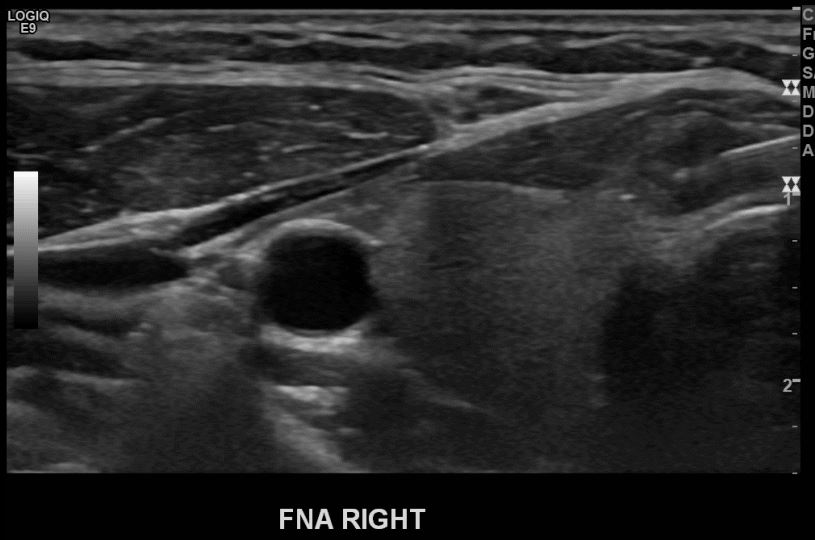

상기환자 검진이상으로 추적검사위해 내원하신 30대초반 여성분으로 의심스러운 우엽혹 세포검사진행후 갑상선암으로 진단되었습니다